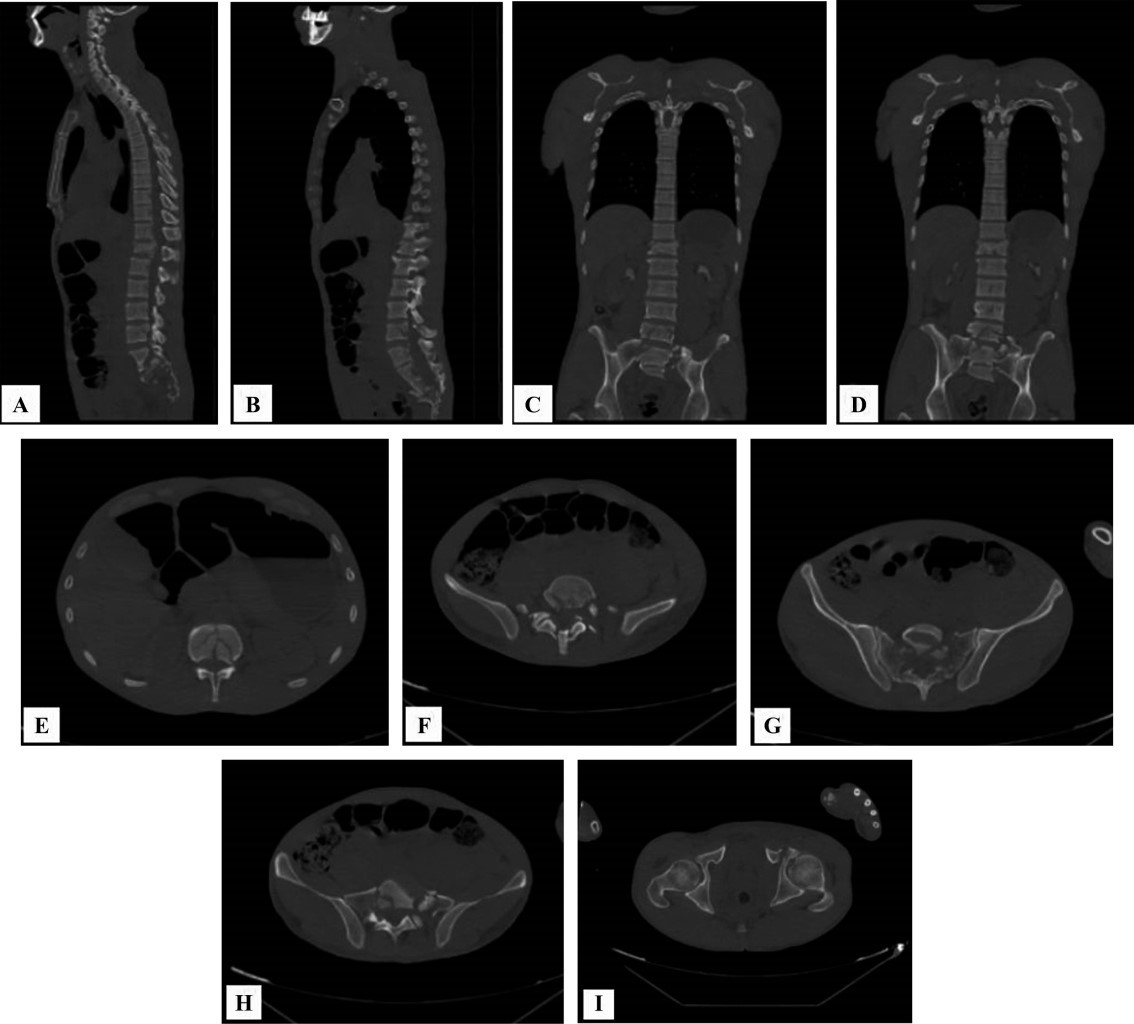

Se realizan radiografías de control serie pélvica y radiografías de codo y columna (Figura 2). En estas series se evidencian disrupción del anillo pélvico anterior del lado izquierdo, fractura articular de húmero, con fractura en arcos costales cinco y seis; serie radiográfica de Judet. Posteriormente se realizan tomografía axial computarizada (TAC) con cortes axiales sagitales y coronales de columna con pelvis (Figura 3) y reconstrucción 3D (Figura 4) donde se observa fractura del anillo pélvico tipo C de Tile por mecanismo de cizallamiento vertical en donde se observan fracturas de rama iliopubiana en zona III de Nakatani e isquiática ipsilateral izquierdas con fractura multifragmentada de sacro con patrón H asociada a hundimiento de plataforma de S1 y fracturas transforaminales bilaterales que se unen a nivel de S2-S3 clasificada como C3 por AO. Se encuentran también fracturas de los cuerpos vertebrales que fueron clasificadas acorde con la propuesta de AO, L1 por compresión tipo A4, fractura de L5 por distracción tipo B2 además de fracturas de las apófisis transversas de L4, L3 y L2 secundarias al cizallamiento vertical tipo A0.

El paciente es estabilizado y se ingresa a la unidad de ortopedia para la realización de manejo quirúrgico definitivo. Se realiza para la columna y pelvis una planificación preoperatoria tridimensional con ayuda de realidad virtual (Figura 5), en donde se decide por la pérdida de capacidad de carga de la columna lumbar y su limitación de transmisión de cargas hacia la pelvis, realizar con un abordaje posterior en línea media de región de columna, una instrumentación posterior espinopélvica larga con colocación de tornillos transpediculares bilaterales en T12, L2 y L4; así como instrumentación de pedículo derecho en L5 y pedículo izquierdo en L3, además de instrumentación de ilíaco bilateral con tornillos en corredor LC2, con barras laterales y dando distracción entre T12 y L1 y entre L5 e ilíacos, se coloca además un crosslink para incrementar la rigidez del constructo de nuestra instrumentación espinopélvica larga. Además, se procede en el mismo tiempo quirúrgico una reducción abierta y directa con osteotomía del olécranon tipo Chevron y fijación interna del húmero distal bajo principio biomecánico de sostén con doble placa de reconstrucción en configuración medial y lateral con placas paralelas (Figura 6). En el postquirúrgico inmediato se realiza tomografía con supresión de metales y reconstrucción 3D para valorar adecuada posición de los tornillos transpediculares (Figura 7).